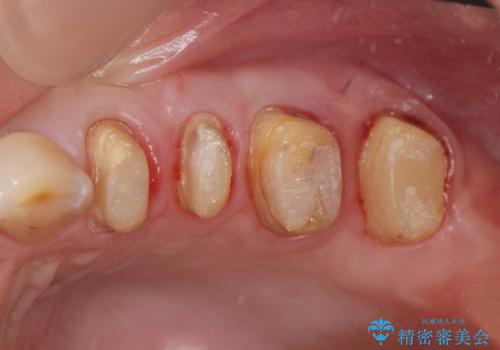

放置した虫歯 根管治療 フルジルコニアクラウン

- 虫歯治療を途中で中断し放置した歯の治療再開を希望され来院されました。

樹脂やクラウン・銀歯の老朽化がみられるため、丁寧に除去を行い根管治療を行ったのち、歯軋り・厚みの少なさを鑑みフルジルコニアクラウンによる補綴を計画します。